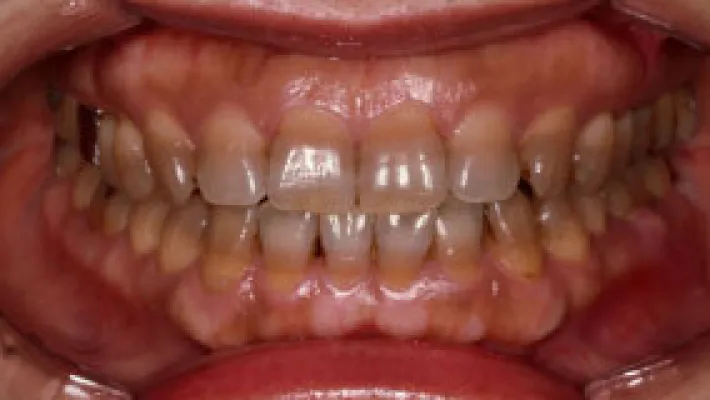

Case3. 上前歯4本ラミネートベニアと2本オールセラミッククラウン + ホワイトニング

施術前

施術後

テトラサイクリン歯の色と古いクラウンを改善した症例です。下前歯や全体をホワイトニングしました。上前歯中央2本は元々のセラミッククラウンをオールセラミッククラウンにし、周りの4本を削らないラミネートベニアで色調を統一し改善しました。

オールセラミッククラウンと削らないラミネートベニアの組み合わせによる治療は当院で数多く行っています。

*下前歯にはラミネートベニアを行えません。ホワイトニングかセラミッククラウンの選択肢になります。